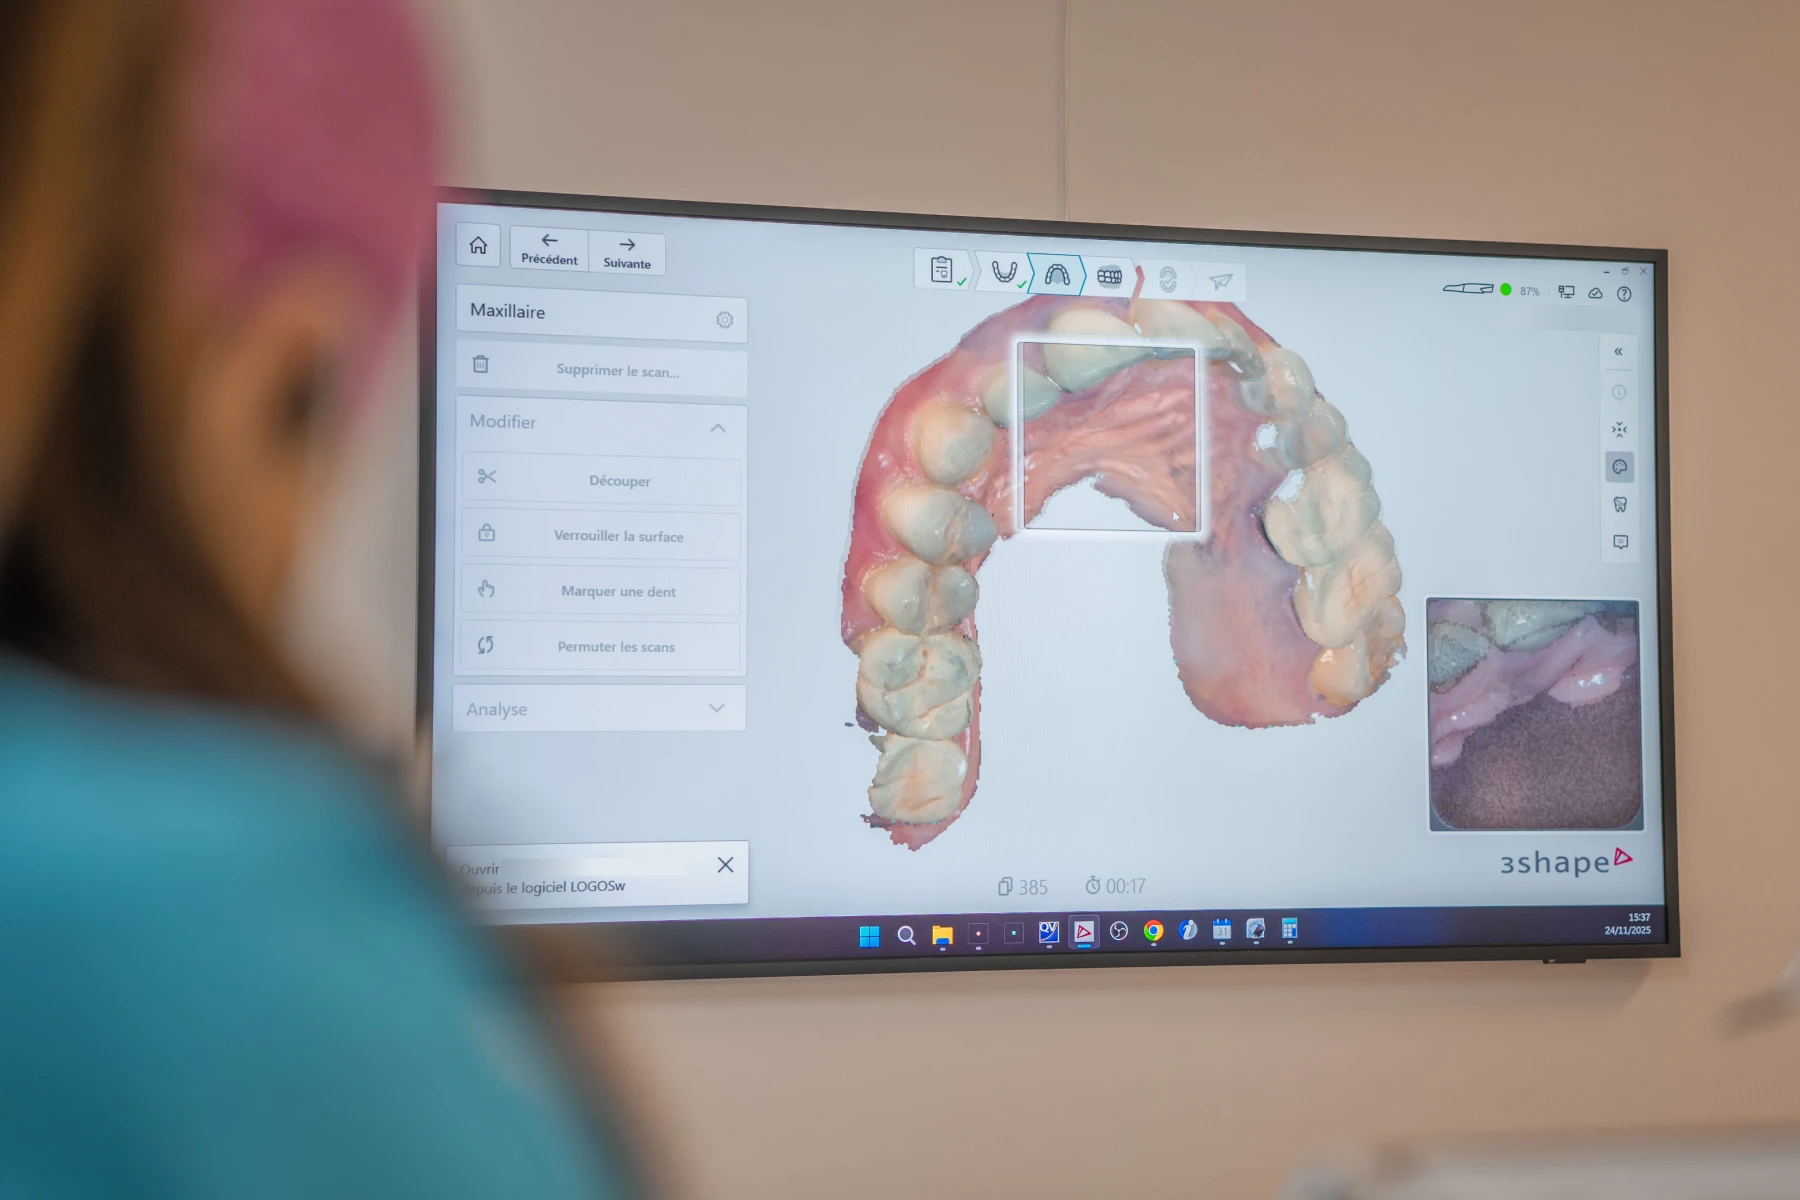

Scanner intra-oral

L’empreinte optique numérique est une technologie de pointe qui permet l’obtention d’image en direct d’une ou de plusieurs dents en trois dimensions et à l’aide d’une caméra intra-buccale couplée à un ordinateur.